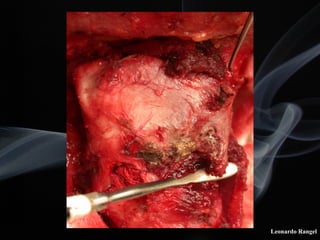

!TÉCNICA

LPSC

Leonardo Rangel

Articulação crico-tireóidea

! A incisão de abertura superior da laringe deve

ser exatamente ao nível do pecíolo.

! No lado do tumor, a mucosa subglótica ao nível

da cricóide, deve ser descolada juntamente com

o pericôndrio interno.

! É necessário a preservação do nervo laríngeo

(recorrente) e de uma aritenóide no lado

normal.

! A aproximação da cartilagem cricóide ao osso

hióide deve ser efetuada num mesmo nível.